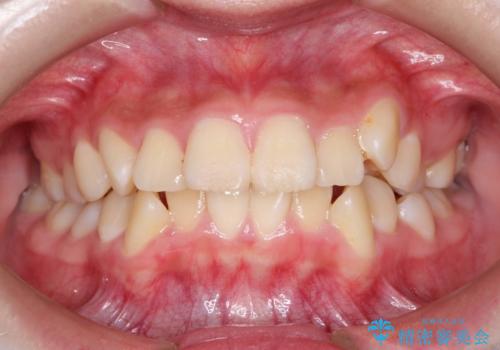

- 上下左右4本の小臼歯を抜歯、ラビアル・ワイヤー矯正を計画した。

抜歯をして第1小臼歯分のスペースを獲得することにより、ガタつきの改善と前歯のリトラクトをおこない、横顔の印象もすっきりとし、整ったEラインを作ることができました。